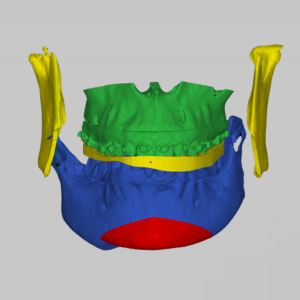

แก้ปัญหาการสบฟันที่มีปัญหารุนแรง ร่วมกับความผิดปกติของขากรรไกร

วางแผนการรักษาด้วยเทคโนโลยีคอมพิวเตอร์ 3 มิติ

สแกนช่องปาก เพื่อเก็บข้อมูลอย่างละเอียด ด้วยการสแกนฟัน 3 มิติ ทำ X-ray หรือ CT Scan

วางแผนการรักษา ด้วย AI Technology และ 3D Computer Imaging